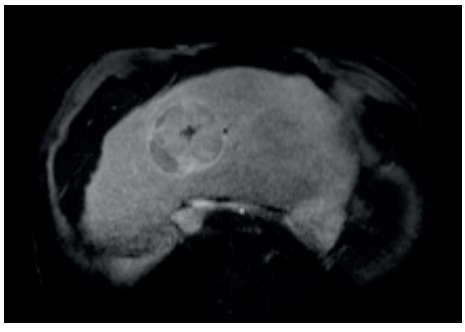

Diagnóstico não invasivo

O CHC é uma das poucas neoplasias que pode ser diagnosticada sem biópsia, desde que o paciente seja de risco (cirrótico/HBV) e apresente o padrão vascular típico em exame dinâmico (TC ou Ressonância Magnética trifásica).

Classificação LI-RADS (Liver Imaging Reporting and Data System)

- LI-RADS 3: Probabilidade intermediária.

- LI-RADS 4: Provável CHC.

- LI-RADS 5: Definitivamente CHC. (Trata-se sem biópsia).